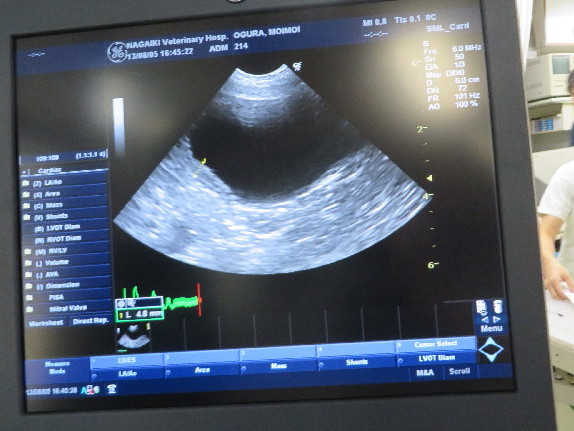

エコーは画像診断がご専門のTRVAの中村先生がやってくださいました。

膀胱の一部が炎症で厚くなってしまっています。

(左のほうの黄色い破線部分が厚くなっている箇所)

でもこれはただの炎症だそうで、大丈夫だそうです。

ここは膀胱の下だったか(上だったかも?)で、ここはガンができやすい部位ではないそうです。